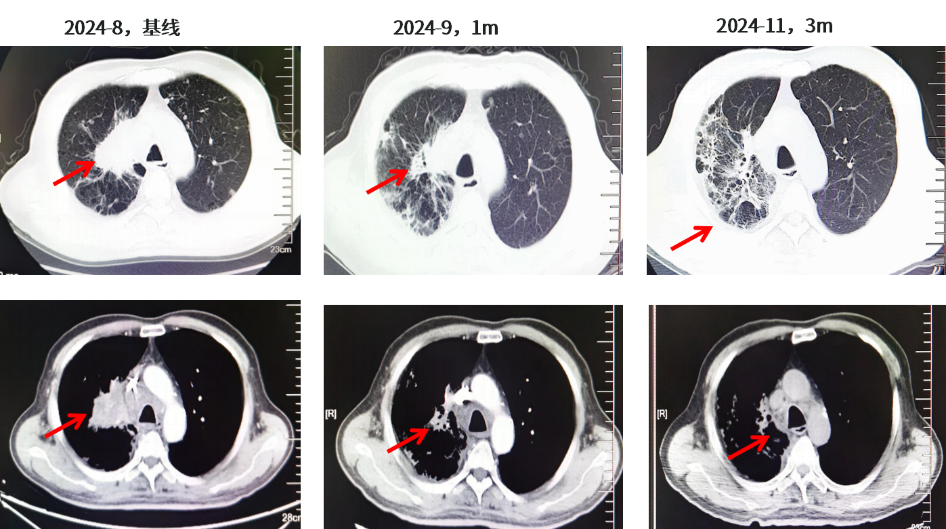

患者于2024年8月14日-2024年11月接受伏美替尼80mg QD联合伯瑞替尼100mg BID靶向治疗,治疗1个月后2024年9月11日复查右肺肺门靶病灶明显缩小(57mm→25mm),肾上腺病灶明显缩小(右侧48mm→36mm;左侧46mm→34mm),疗效评估达PR。头颅MR示颅内病灶消失,疗效评价达CR。患者有肺间质纤维化既往史,右肺间质性改变加重,不除外药物相关不良反应,患者无明显不适症状。主要不良反应为I级间质性肺炎,I级肌酐增高。肿瘤标志物:CYFRA21-1由40.61降至3.11,CA19-9由1575降至23.65。

图3.胸部CT结果(2024.08基线、2024.09、2024.11)

图4.肾上腺CT结果及颅脑MR结果(2024.08基线、2024.09、2024.11)